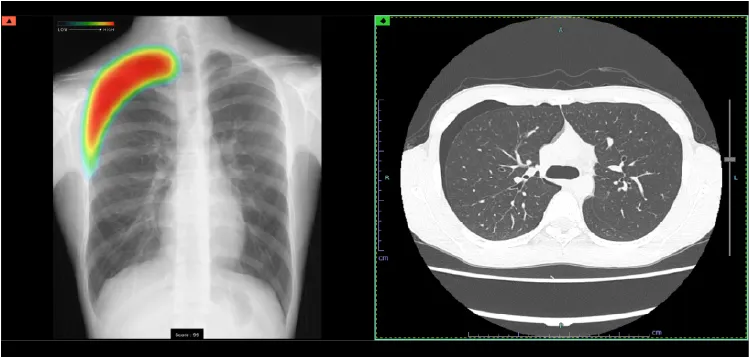

CT(コンピュータ断層装置)

CTは Computed Tomography(コンピュータ断層撮影) の略で、X線を使って体の断面を撮影する装置です。体の内部構造を詳しく画像化できるため、さまざまな病気の発見に役立ちます。近年の技術進歩により、0.5mm間隔で断層画像を撮影できるため、ごく小さな病変も見つけることが可能になりました。また、得られた断面画像を重ね合わせることで、立体的な3D画像を作成することもできます。さらに、必要に応じて 造影剤 を使用すると、腫瘍などの病変部位がより明瞭に写り、周囲の血管の走行や栄養血管の状態を詳しく把握することができます。ただし、造影剤には副作用の可能性があり、また腎機能が著しく低下している場合には使用できないことがあります。造影剤を使うかどうかは、検査内容に応じて医師が判断します。

GEヘルスケア・ジャパン株式会社 Revolution Maxima

当院ではGE社製の64列マルチスライスCTを導入しています。被ばく低減可能な逐次近似画像構成法ASiR-VソフトウェアやAI技術を駆使した次世代ワークフローを搭載した最新のCTで検査が行えます。